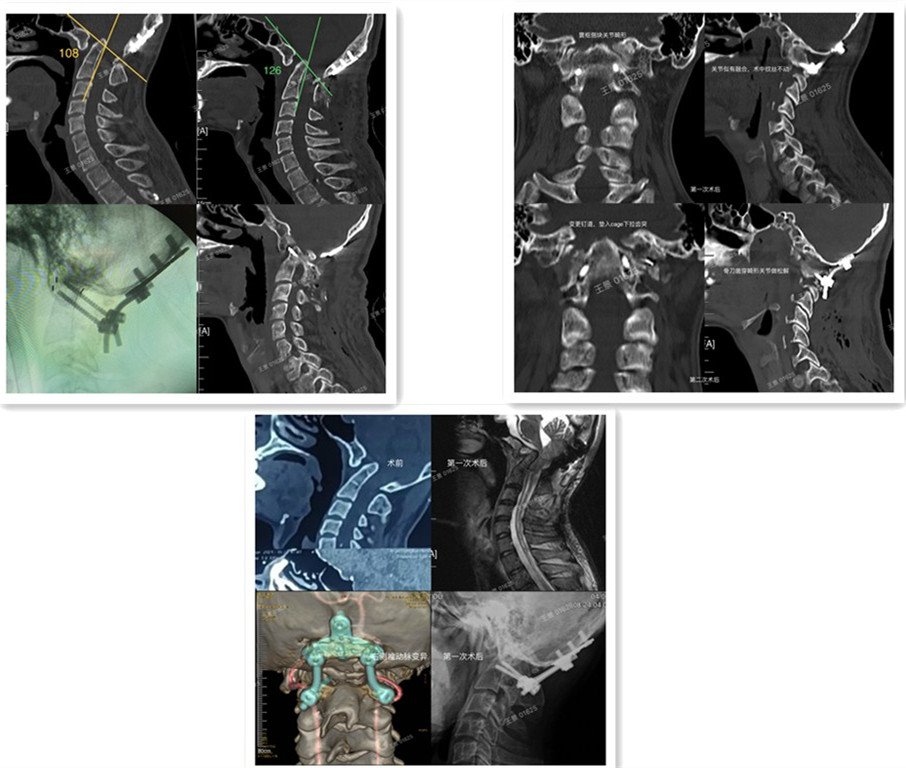

王景为患者完善相关检查,明确诊断为寰枢椎不可复性脱位、Chari I型畸形、脊髓受压、枕颈融合术后、椎动脉变异,手术治疗风险和难度极高。经过详细术前准备,在全麻下为患者实施寰枢椎不可复性脱位后路复位固定融合翻修手术。术中暴露颅底及椎体骨性结构,拆除失效的内固定装置。在显微镜辅助下,松解双侧侧块关节,置入椎间融合器解除脊髓压迫,并行后方植骨融合。术后患者的齿突斜坡角由术前的108°增加到126°,脊髓压迫症状明显改善,术后5天康复出院。